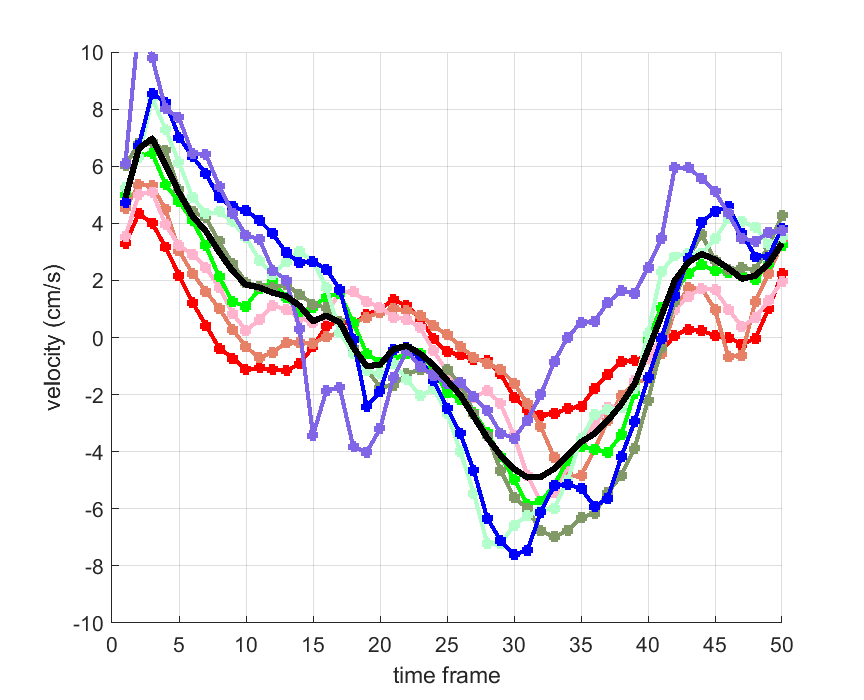

Time courses of the estimated translational component per subject, frame, slice and volume along the 3 velocity directions x, y and z are presented in Fig.6 - Fig.8.